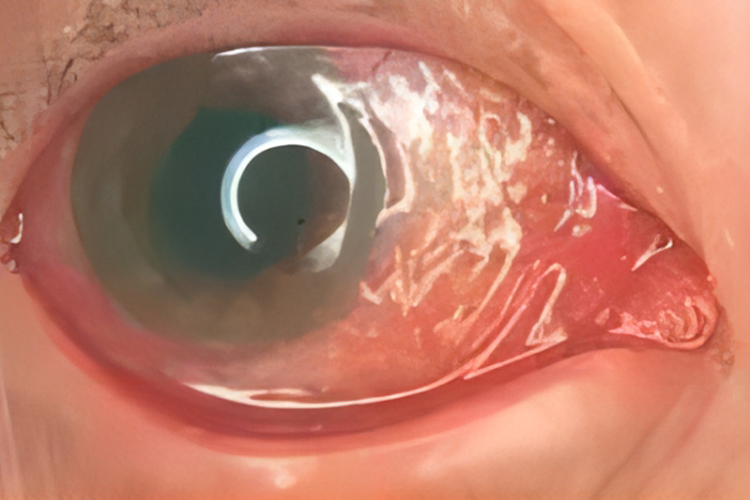

淋菌性结膜炎会出现畏光、流泪、眼睑高度红肿、发热、肿痛,结膜充血,球结膜水肿呈堤状围绕角膜,严重者会突出于睑裂之外,导致眼结膜类似溃疡样改变,还会合并角膜炎出现角膜穿孔。